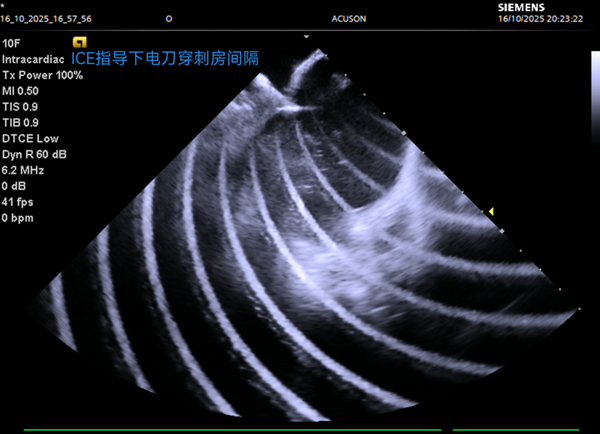

官方微信

手術(shù)團(tuán)隊(duì)對(duì)兩名藏族患者進(jìn)行了精準(zhǔn)治療,其中一位52歲房顫患者,在ICE引導(dǎo)下完成左心房建模與肺靜脈隔離,全程零射線;另一位49歲患者成功轉(zhuǎn)復(fù)正常心律。

湯陽副主任醫(yī)師介紹:“房顫在高原地區(qū)高發(fā),傳統(tǒng)治療受限于設(shè)備與技術(shù),患者常面臨輻射風(fēng)險(xiǎn)和手術(shù)痛苦。此次引進(jìn)的零射線電刀穿刺技術(shù),結(jié)合三維建模與實(shí)時(shí)心包監(jiān)測(cè),不僅精準(zhǔn)安全,更大幅減輕了患者不適,為高原地區(qū)房顫治療提供了可靠的新路徑”。